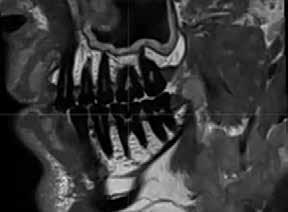

Magnetic resonance imaging (MRI) has been a staple in medicine and dentistry for many years. In dentistry, it serves a somewhat confined role in imaging the temporomandibular joints (TMJ) and occasionally the head and neck, including cysts or tumors. Dental MRI research and publications on these indications, as well as more “traditional” dental imaging tasks such as caries or periapical lesion detection, have progressed steadily since the mid-1980s, followed by a rapid increase in published papers in the early 2020s. These studies have long demonstrated the utility of MRI TMJ and cyst/tumor imaging, as well as the promise of MRI for essentially the entire range of dental imaging indications. Indications include caries, periapical disease, periodontal disease, growth and development/

The newly formed Orofacial MRI Center (OMRIC, dentistry.umn.edu/omric) at the University of Minnesota School of Dentistry is home to the first dental-dedicated MRI (ddMRI) unit in North America and the second installation of its kind in the world. Researchers Drs. Don Nixdorf and Laurence Gaalaas have an extensive track record in dental MRI research and development. Still, they are thrilled to have as an imaging tool one of the very first dental-dedicated MRI units, a Siemens MAGNETOM Free.

Max Dental Edition* MRI scanner. In collaboration with Dentsply Sirona and Siemens Healthineers, Nixdorf and Gaalaas secured a multi-year research agreement and constructed a physical imaging center around a Free.Max MRI unit. Beginning in early 2025, they initiated research studies to investigate the utility of ddMRI diagnosis in patients with endodontic, orthodontic and TMJ conditions. Such work will establish the utility of an experimental dedicated extraoral dental MRI coil and support proven indications for ddMRI imaging in endodontic, orthodontic, TMJ and other dental patient populations.

For those who need a refresher or those who have never truly understood how MRI works, the physics and engineering involved are remarkable. The four basic steps to performing MRI are 1) Put a patient or patient’s body part in a strong magnet field, causing protons (hydrogen nuclei) in the patient to align with the magnetic field. 2) Apply a radiofrequency (RF) pulse at a specific frequency, then, in a phenomenon of physics, all of the protons in the patient previously aligned with the magnetic field realign with the RF pulse and absorb some of the transmitted RF energy. 3) Stop the RF pulse and record any RF energy released back by the patient. It turns out that when tissue protons absorb RF energy, they release it back into their surrounding environment in two distinct ways (T1 and T2) and at variable rates based on surrounding tissue characteristics. Repeating this process multiple times while intentionally altering the initial strong magnetic field with secondary magnets (called gradient coils), all while recording this released signal with an MRI coil (think antenna) allows the system to back-calculate 1) a signal representing relative density of protons or other tissue characteristics and 2) the spatial location of that signal, all together letting us create diagnostic images representing anatomy, disease and at times, tissue function.

which perform notably better at imaging hard tissues such as bone and teeth, compared to more traditional MRI sequences.

While most dentists are likely familiar with the basics of how information is displayed on an MRI image, the adoption of ddMRI will require a mindset shift for virtually all dental team members who may utilize this new technology in their respective clinics. First, the grayscale is fundamentally different from that used for all X-raybased imaging. In MRI, soft tissues are commonly displayed as gray or bright white signals, while hard tissues, such as teeth and bone, are shown as very dark gray or black signals; air remains black. Furthermore, MRI offers the option to select from a variety of different sequences, each of which can produce a slightly different tissue grayscale and corresponding image. Some sequences, such as T1 or PD, do an excellent job of demonstrating detailed anatomical relationships. Other sequences, such as T2, do an excellent job of demonstrating the presence of fluid accumulation within tissues. Many available “Fat sat” or “STIR” sequences may selectively “zero out”, “suppress”, or “saturate” the signal of fat, which is traditionally very bright white on MRI images, to reveal the otherwise hidden signal from subtle fluid accumulation or inflammatory changes. Some of these specialized sequences may not accurately depict anatomic relationships, but are designed to be exceptionally sensitive to detecting inflammatory changes with a bright signal. The short T2 sequences mentioned above are beginning to depict the hard tissue differences between cortical bone and medullary bone, as well as the differences between tooth dentin and enamel. Developing, learning and using all these different sequence choices in concert is where the real research and diagnostic potential of ddMRI lies. t

Proton density image of horizontally impacted tooth #17.

Proton density image of TMJ demonstrating anterior disc displacement, disc fold and joint effusion.